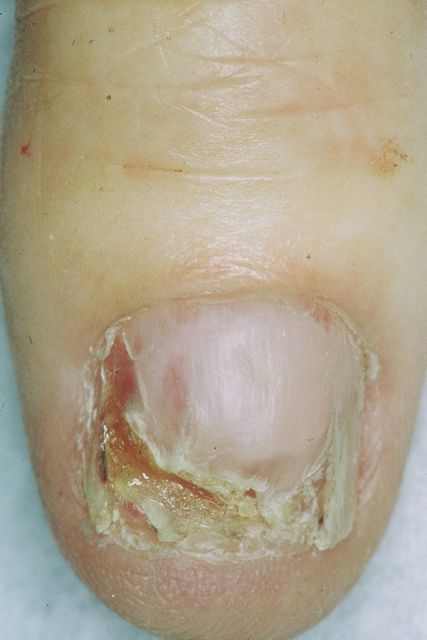

Amelanotic melanoma appears as a lesion that has little or no color (non-pigmented) or may appear red, pink or scarlike-white.  It has an asymmetrical shape, and an irregular faintly pigmented border.

Any of the types of melanoma may be amelanotic, but a particular amelanotic variety is called desmoplastic melanoma (DM).  DM is most commonly found in acral lentiginous melanomas located subungually (under the nailbed), in lentigo maligna lesions  or after cryotherapy for treatment of lentigo maligna. Desmoplastic is a unique melanoma in that the overall survival of patients with thick (>4mm) tumors appears to be longer than that of the other melanoma types (Zettersten et al, 2002).  It appears on the head and neck, up to 40% recur locally, and most often metastasizes to the lung while sparing the regional lymph nodes (Jaroszewski et al, 2001). Recurrence rates are high because the tumor cells have a spindle shape making them vulnerable to inadequate surgical excision (Liu et al, 2003).